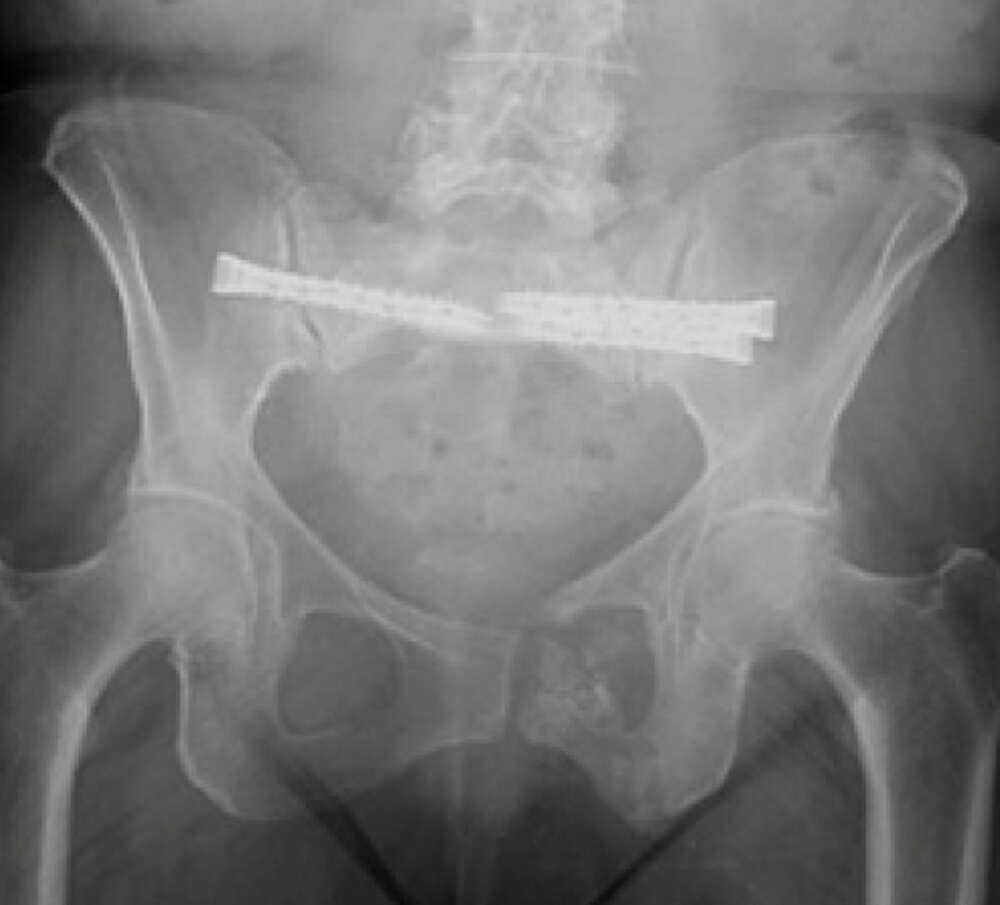

Lumbopelvic Instability after Chronic Sacral U- Fracture

Patient History:

• Fall 3 months prior

• Managed non-operatively by outside hospital

• 10/10 pain; difficulty ambulating x 3 mo

• MRI done and self-referral to IR for sacroplasty

• Referred to ortho by IR for pelvic fixation

Diagnosis:

• Chronic Sacral U-type fracture with kyphotic deformity

• Anterior ring disruption

• Osteopenia